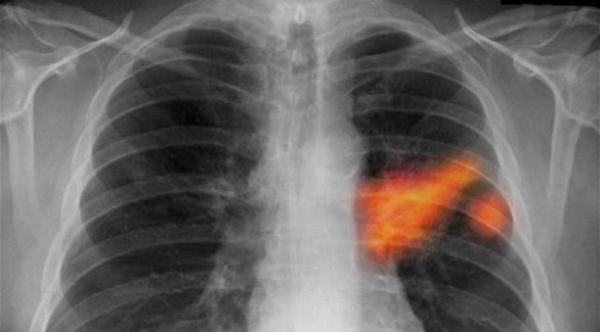

وبفضل التحسين المستمر لتقنيات التصوير خلال السنوات الأخيرة، يمكن لمرضى السرطان الاستفادة أيضاً من علاجات يشارك فيها أخصائيون في علم الأشعة.

وبحسب الاخصائية في الأشعة التدخلية أفشين غانغي، في ستراسبورغ شرق فرنسا، فإن هذه التقنيات الجديدة توفر "الطريق الأقصر إلى الورم"، بهدف تدميره بالطريقة الأفضل من دون اللجوء بالضرورة إلى الجراحات التقليدية.

ويمكن تالياً استبدال هذه الجراحات بتقنيات الاستئصال الحرارية خصوصاً، عن طريق استخدام الترددات الرادوية والليزر والموجات الصغرى والعلاج بالتبريد أو الموجات فوق الصوتية المركزة، (يتم فيها تركيز الطاقة الصوتية على الهدف لتدميره).

وتسمح هذه التقنيات المستخدمة بشكل أساسي حالياً في معالجة أمراض الكلى والكبد والبروستات، بالتصدي لأمراض في أعضاء أخرى في البطن لكن أيضاً لأمراض الثدي، بحسب غانغي.